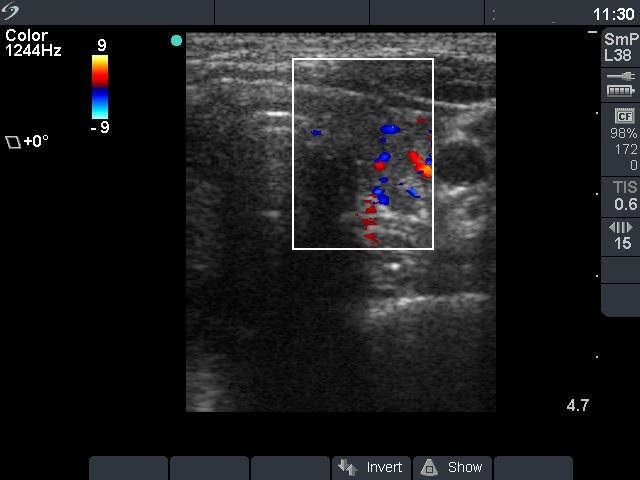

Left lobe, transverse scan, color Doppler mode. The vascularization is slightly increased.